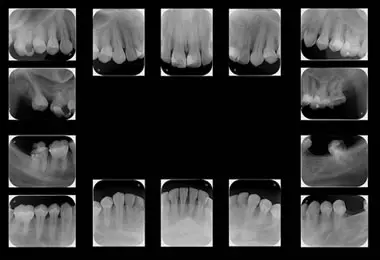

Radiografía seriada periapical AB Imágenes Dentales

Seriadas Dentales: Precisión Detallada para un Diagnóstico Completo.

Fundamental para la detección temprana de caries, enfermedades periodontales, lesiones periapicales, fracturas dentales y condiciones óseas específicas. A través de múltiples tomas, obtenemos una imagen completa de la anatomía dental y las estructuras de soporte.